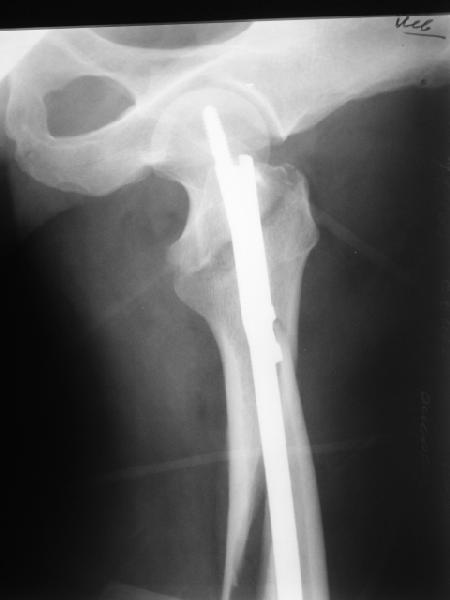

Реконструкционный гвоздь.

DK> фиксацию провели антеградным штифтом.

Да, сейчас это и у нас самый напрашивающийся выбор. Сделали гвоздем ChM, картинки в приложении.

У молодых реконструкционный гвоздь самое то. При остеопорозе надо что-то помассивнее.